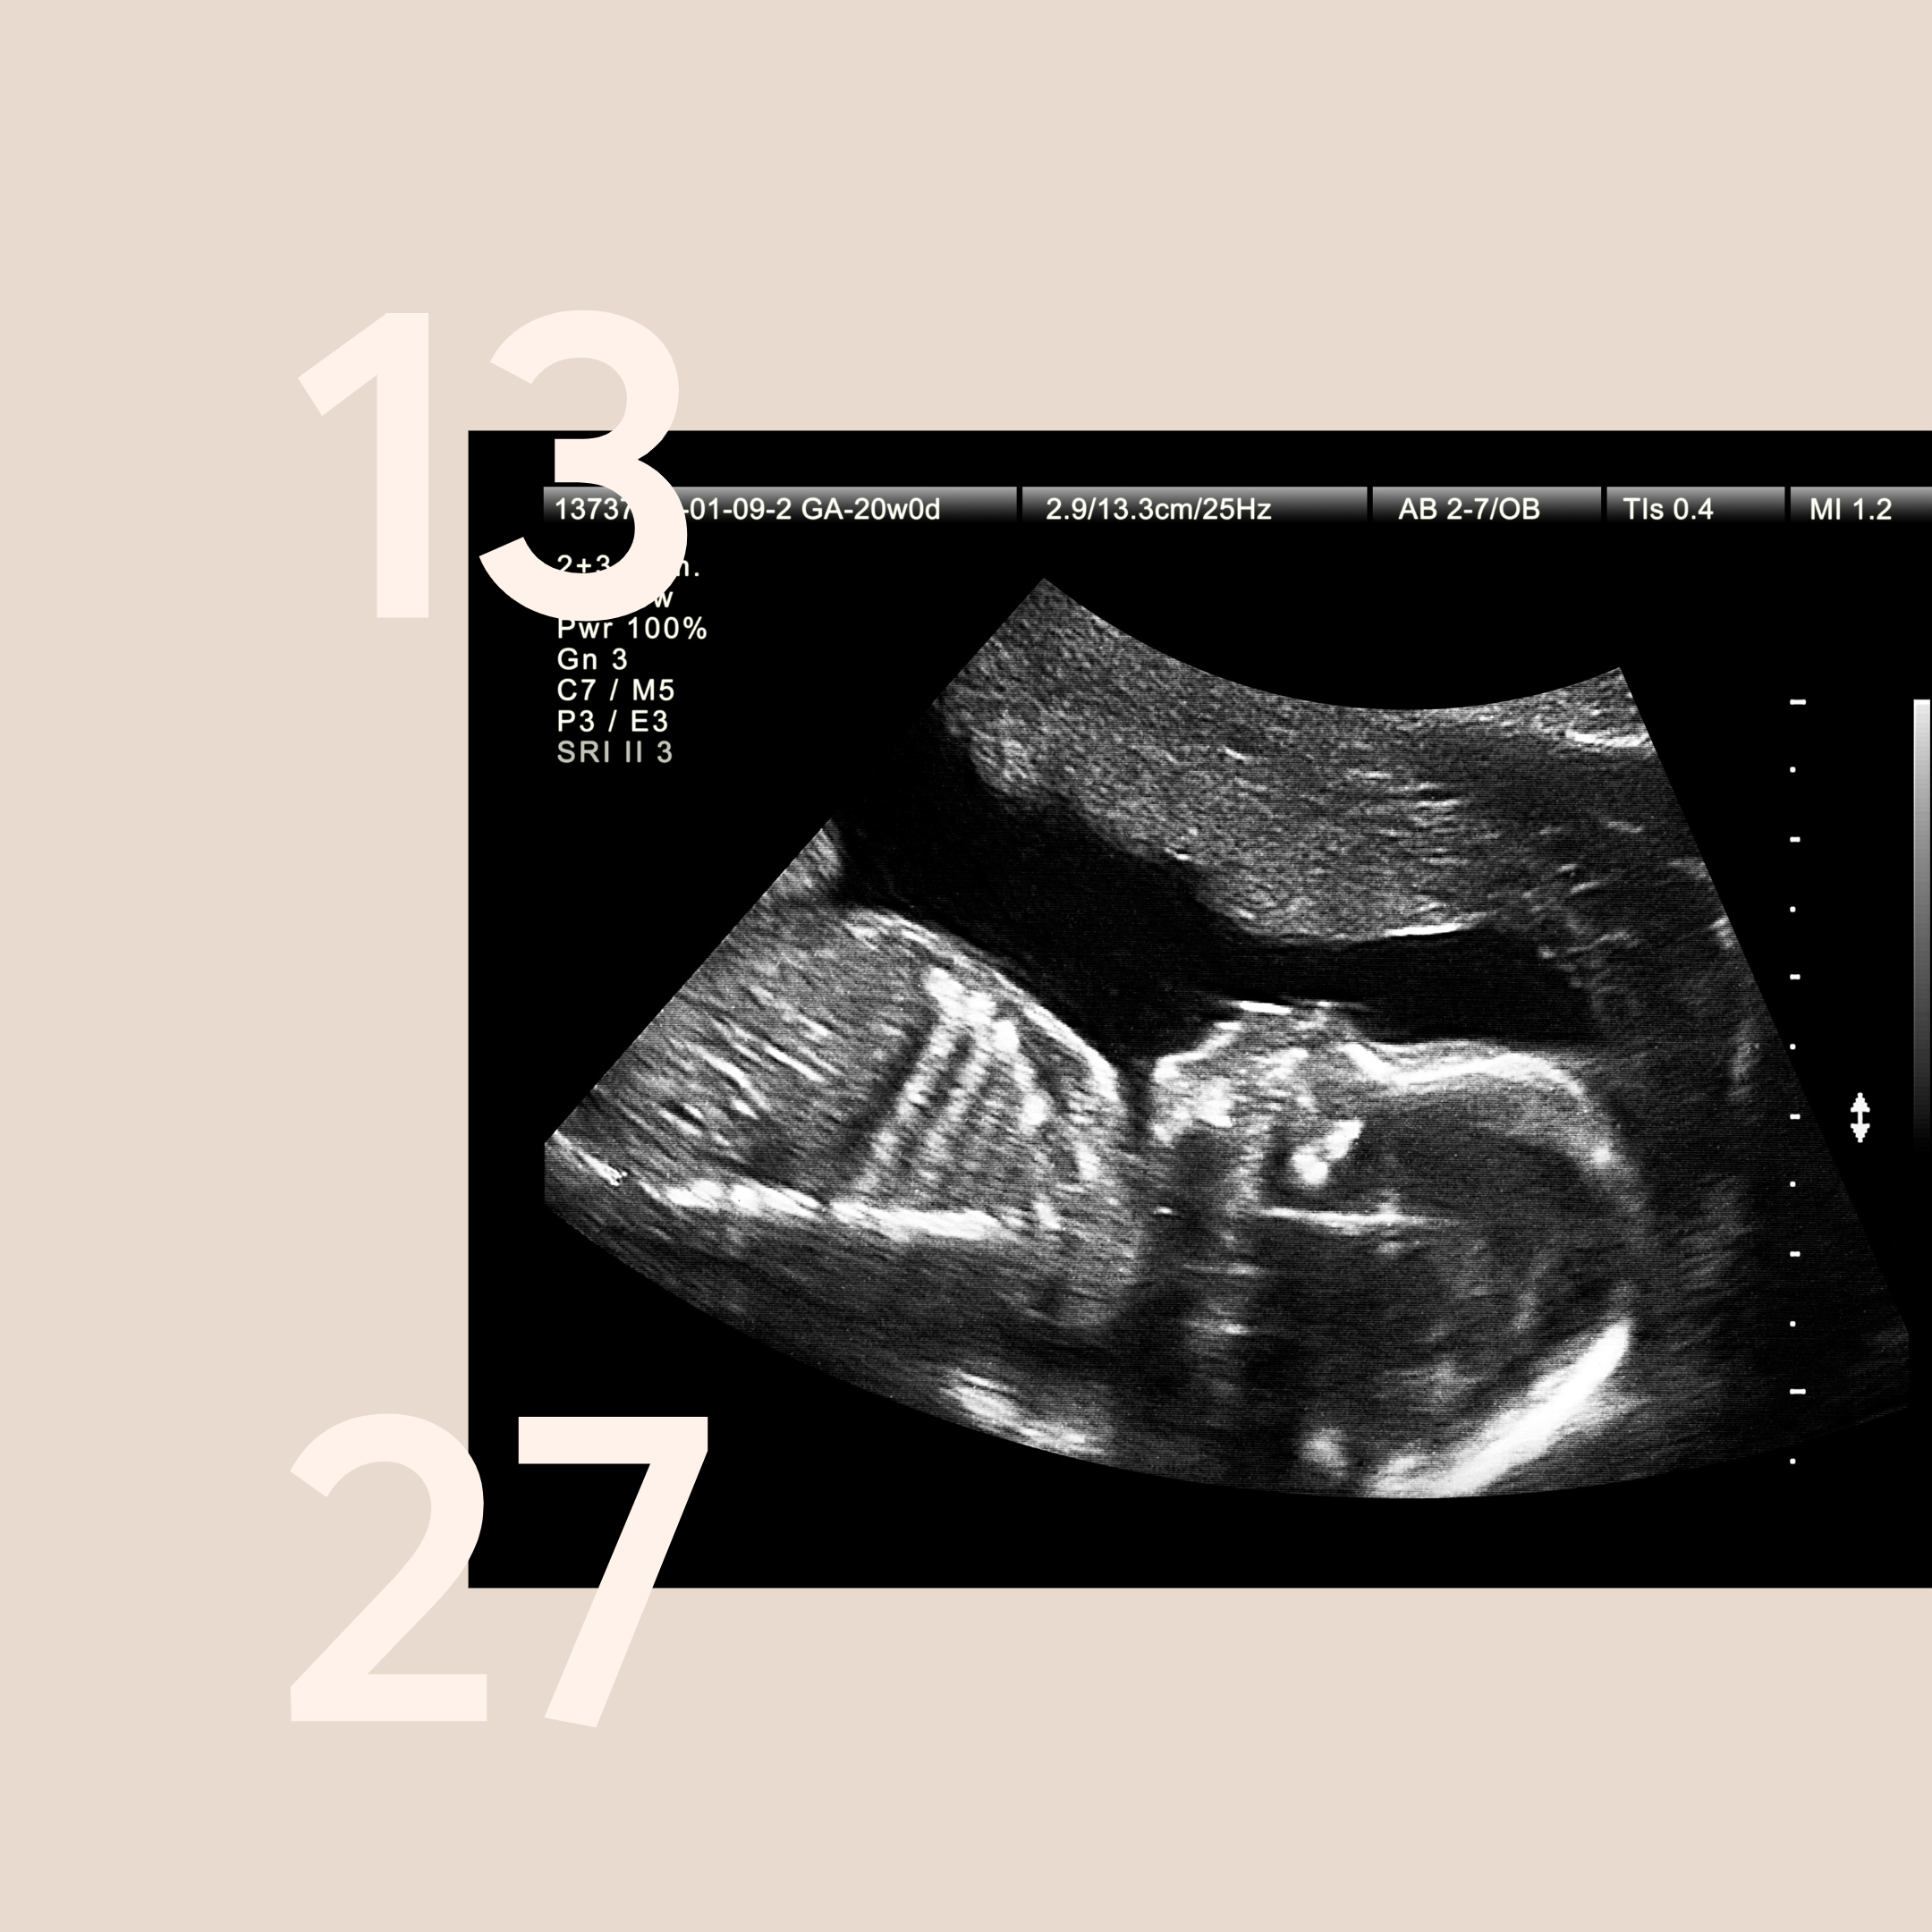

3. Anatomy Scan:

Around the midpoint of the second trimester, you will undergo an anatomy scan. This detailed ultrasound examination assesses your baby's development, including their organs, limbs, and overall well-being.